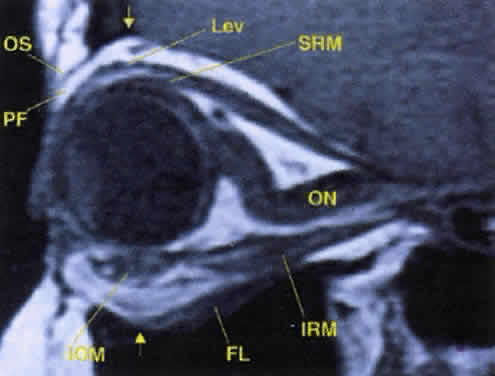

Tables 10 and 11 summarize the important features of each of the cranial nerves supplying the orbit (Fig. 16, see Fig. 12). Several points are worth mentioning. First, the optic nerve assumes an S-shaped course within the orbit. Because the intraorbital nerve is about 25 mm long and the distance from the back of the globe to the optic foramen is 18 mm, 7 mm of slack remains. This degree of potential mobility allows the nerve to remain unaffected during ocular rotations and provides a cushion for axial proptosis (Fig. 17).

Fig. 17. The optic nerve (ON). A parasagittal MR image demonstrates the 7-mm excess of intraorbital optic nerve, seen as an S shape. Also note the perpendicular relation of the inferior oblique muscle (IOM) to the inferior rectus muscle (IRM). Other findings of anatomic interest in this image include the levator (Lev), the superior rectus muscle (SRM), the orbital septum (OS) arising from the arcus marginalis, and the preaponeurotic fat pad (PF) between the septum and the levator. Note that the orbital floor (FL) is angled upward by 15° to 20° from anterior to posterior.